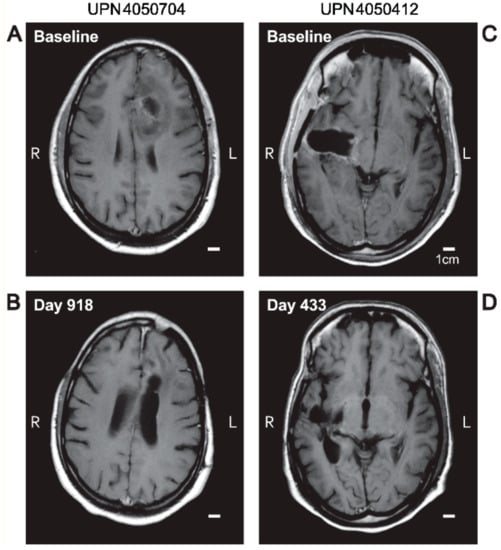

3.3. Edema and Pseudo-Progression in OT101-Yreated Target HGG Lesions